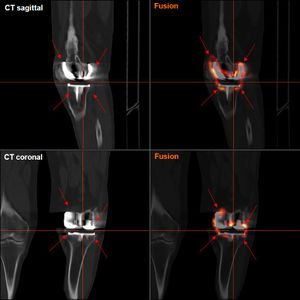

يقوم الطبيب بارسال المريض لاجراء فحص تصوير للركبة، أحياناً يكتفي الطبيب باجراء فحص تصوير بالأشعة السينية، ولكن غالبا يتم اجراء فحص التصوير المقطعي المحوسب للركبة أو التصوير بالرنين المغناطيسي.